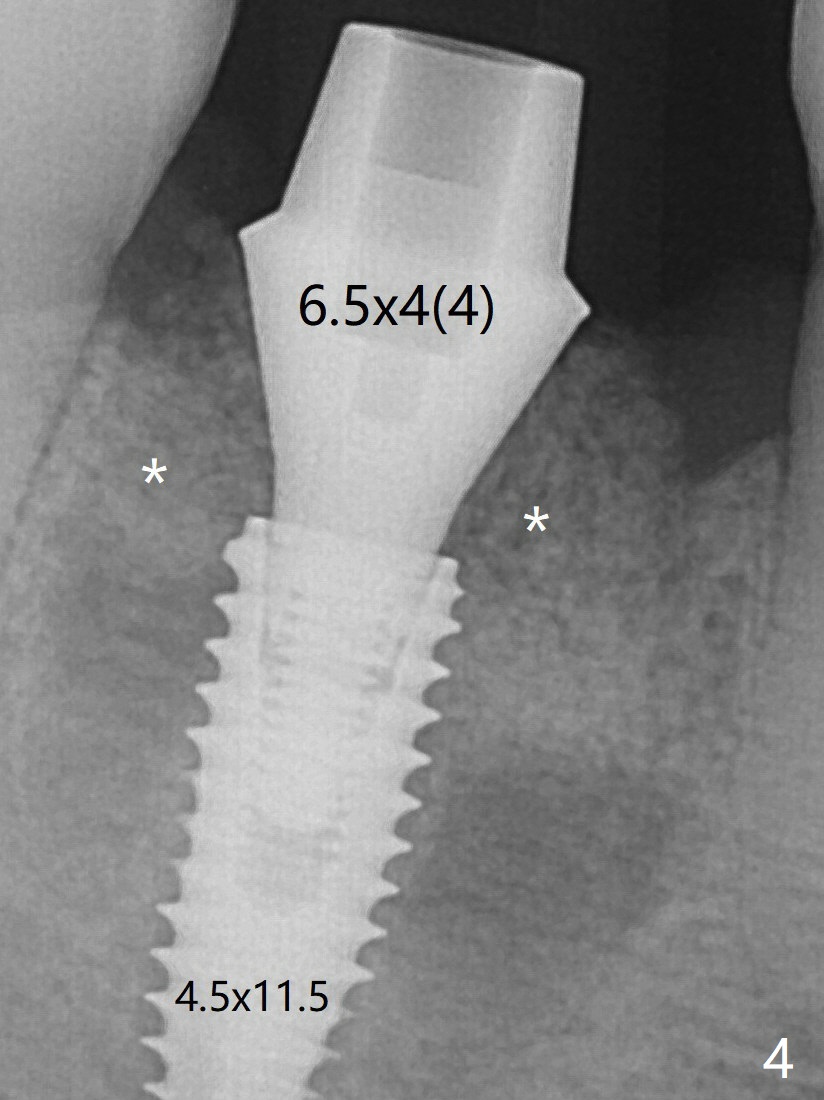

When a definitive implant (Fig.4: 4.5x11.5 mm( *: bone graft)) is placed with primary stability, there is an apical space (Fig.5 white double arrows). There is moderate postop pain. A shorter implant (10 mm) should be tried when the bone is dense. It will be associated with less pain. The fistula disappears 7 days postop (Fig.6). Although the patient appreciates that the pain is gone, there is atrophy mesiobuccally 2 months postop (Fig.7 *). The implant seems to be have been placed too buccally (Fig.8). With loss of the buccal plate, the implant should be placed away from it to prevent periimplantitis. The abutment is changed from 6.5x4(4) to 6.5x5.5 (3) mm with fabrication of a new provisional. The buccal margin is still supragingival 6 months postop and prep lower before impression (to reduce food impaction). The mesial and distal sockets appear to have healed (Fig.9). The bone density around the implant increases 11 months post cementation (Fig.12).